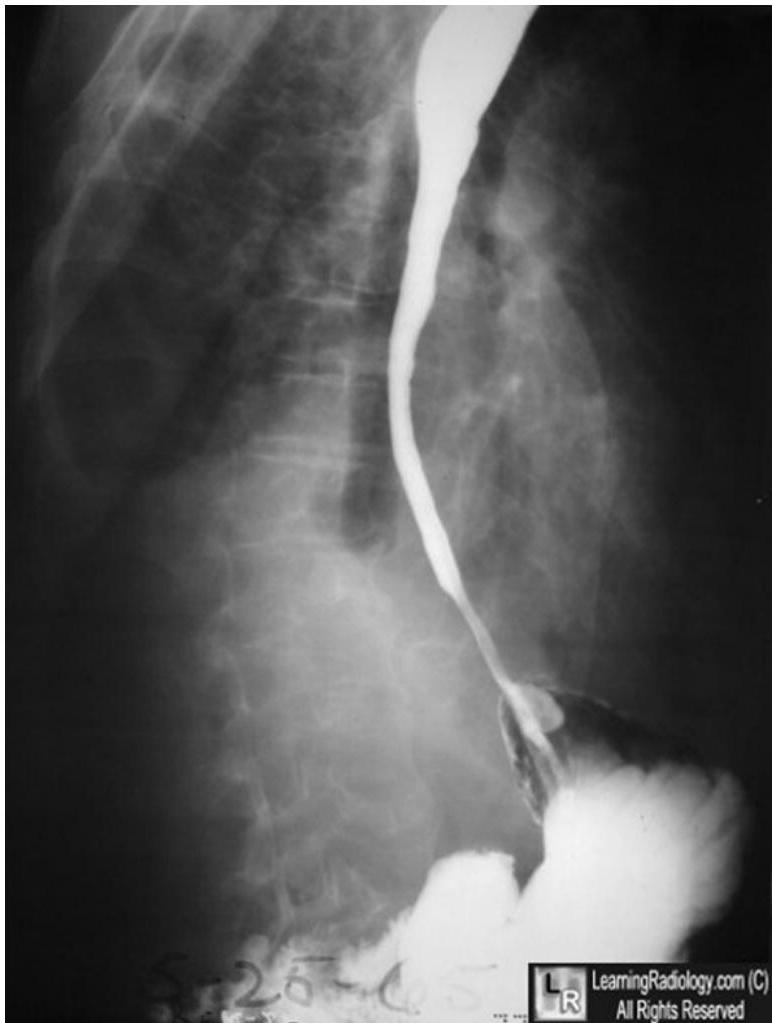

Barium swallow and follow through

- To detect any strictures, ulceration, to rule out intestinal obstruction, or to assess esophageal peristaltic wave.